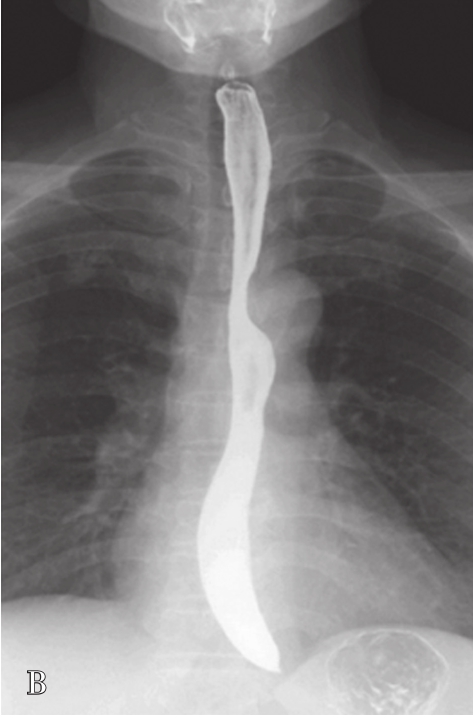

目的在于进一步了解肿大肝脏对胃、十二指肠和结肠肝曲的压迫和移位情况。肝癌患者常伴发肝硬化,应行钡餐检查除外食管、胃底静脉曲张,以及阻塞性黄疸与胃肠道的关系等。

检查前准备:行胃肠道钡餐患者常规均应检查前禁食和禁水6h以上,检查前3天不服用含铁、铋、钙等不透X线元素的药物,以免残留在肠道内影响观察。常规采用钡剂检查(图5-21-33B、图5-21-33C),如有新鲜消化道出血患者禁行钡剂检查,必要时可行泛影葡胺等碘水检查。

图5-21-33 胃肠道钡剂检查图片

A.正常上腹部仰卧前后位,可见胃及肠管内少量积气;B.正常食管充盈像;C.正常站立位胃充盈像。

常规腹部平片对肝硬化诊断价值非常有限,但胃肠道钡餐检查可显示中晚期肝硬化患者食管、胃底蚯蚓状扩张的静脉。食管静脉曲张是门静脉高压的重要并发症,最主要见于肝硬化、门脉系统的血栓形成及上腔静脉综合征。

上消化道钡餐检查可见食管及胃底多发串珠状或蚯蚓状充盈缺损,食管腔轻度扩张,管壁蠕动减弱,病变常始于食管下段,后延及食管中段及胃底,极少数可波及食管上段。按静脉曲张的范围、程度及食管蠕动功能分为轻度、中度、重度。①轻度:静脉曲张最初局限性于食管下段,表现为黏膜皱襞稍增宽,可呈浅锯齿样表现。管腔可收缩排空。②中度:随着静脉曲张的发展,曲张范围超过下段累及中段。静脉增粗迂曲突向管腔,正常平行的黏膜皱襞消失,代之以纵行粗大结节样条状影,进一步表现为串珠状或蚯蚓状充盈缺损,食管边缘凹凸不平,由于黏膜下明显静脉曲张,食管腔被撑开而略显增宽,食管收缩欠佳,排空稍延迟。③重度(图5-21-34):后期静脉曲张扩展到中上段,甚至食管全长。严重的曲张静脉占据食管壁,并使肌层受压迫而退变,食管明显扩展,不易收缩,腔内见形态不一的圆形、环状或囊状充盈缺损,管壁蠕动明显减弱,排空延迟,但管壁仍柔软可扩张。

图5-21-34 重度食管静脉曲张钡剂检查结果

食管全长可见不规则蚯蚓状和结节状充盈缺损,食管明显扩展,蠕动明显减弱,排空延迟,管壁尚柔软